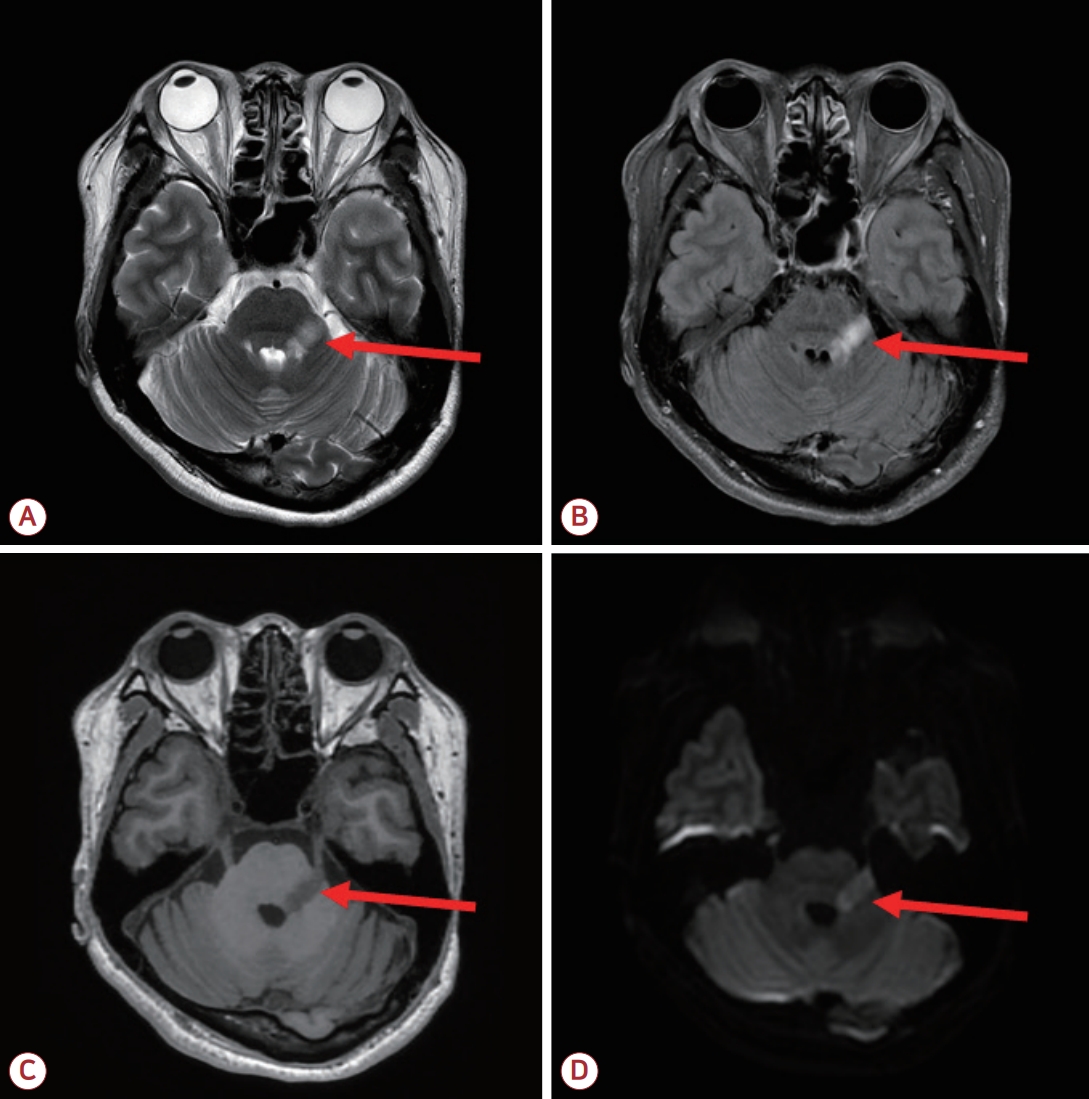

50세 여성 환자가 좌측 얼굴과 입술 저림이 발생한 지 일주일 만에 병원을 방문하였다. 증상은 어지러움, 메스꺼움, 구토를 동반하였다. 뇌 magnetic resonance imaging에서는 좌측 다리뇌(pons)에 T2 강조영상에서 선형 고신호강도를 보였으며 T1 강조영상에서는 저신호강도를 나타냈다. 특히 좌측 삼차신경을 따라 신호 변화가 관찰되었다. 해당 병변을 제외한 다른 부위에서는 다발경화증을 시사하는 T2 고신호 강도 병변은 관찰되지 않았다(Fig.). 뇌척수액 검사에서는 백혈구가 관찰되지 않았으며 올리고클론밴드, AQP4항체 및 바이러스 polymerase chain reaction 검사 결과도 음성이었다. 혈청 면역 형광 유세포 분석법을 통해 수초희소돌기아교세포당단백질(myelin oligodendrocyte glycoprotein, MOG)항체를 분석한 결과 fluorescein isothiocyanate 채널의 평균 형광 강도 비율(mean fluorescence intensity ratio, MFIr)이 3.63으로 확인되어 양성으로 판정되었다. 판정 기준은 다음과 같다: 음성, MFIr≤2.02, 경계 또는 약양성, 2.02<MFIr≤2.61, 양성, MFIr>2.61. 환자는 고용량 스테로이드 치료를 받았으며 증상이 호전되었다. 삼차신경다리뇌징후(trigeminal pontine sign)는 다발경화증에서 흔히 관찰되고 시신경척수염이나 바이러스 감염에서도 보일 수 있다[1,2]. 본 증례는 삼차신경다리뇌징후를 보이는 환자에서 MOG항체 관련 질환(myelin oligodendrocyte glycoprotein antibody-associated disease)이 감별 진단에 포함될 필요가 있음을 시사한다.

Brain MRI reveals a linear hyperintensity on axial T2-weighted (A) and fluid-attenuated inversion recovery (B), hypointensity on axial T1-weighted (C), and hyperintensity on axial diffusion-weighted imaging (D) in the left pons (red arrows), with peripheral diffusion restriction. Notably, signal changes are observed along the left trigeminal nerve (not shown). MRI; magnetic resonance imaging.